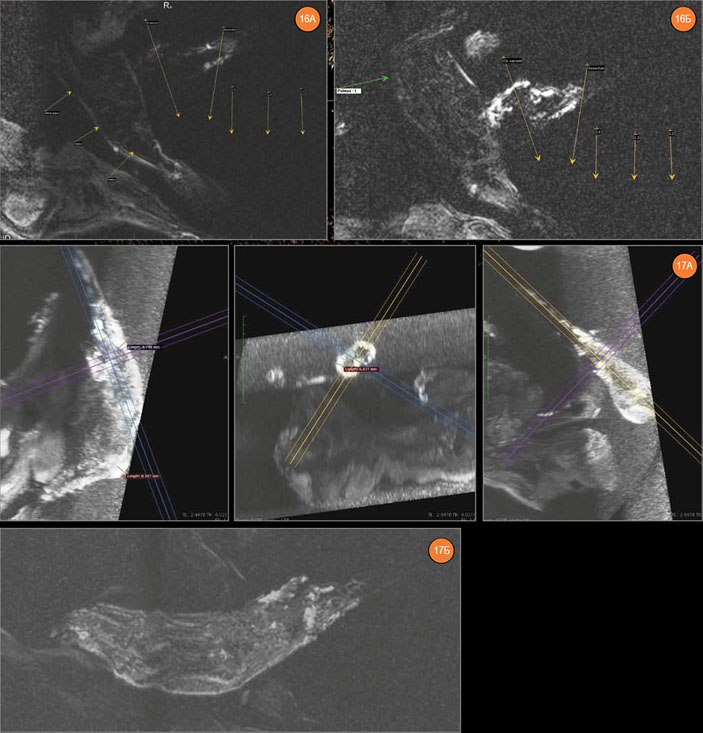

МР-томография также не выявила каких-либо патологических изменений в структуре ребер. Кости левой кисти — без признаков поражения, подкожная клетчатка — без признаков отечности. Кости правой кисти — также без видимой очаговости, но имеется диффузная отечность и утолщение подкожно-жировой клетчатки проксимальнее лучезапястной складки.

Рис. 16. Левая кисть. А — запястные и пястные кости. Б — пястные кости и фаланги. Рис. 17. Правая кисть (проксимальные фаланги, запястные и пястные кости, фрагмент предплечья). Видно диффузное усиление сигнала и утолщение подкожно-жировой клетчатки проксимальнее лучезапястной складки. А — трехпланарная проекция, Б — технология наложения полупрозрачных соседних томографических срезов

Левый локтевой сустав выглядит неизмененным, но в структуре локтевого отростка локтевой кости имеется отечный очаг размером до 9×7×8 мм.

Рис. 18. Левый локтевой сустав. А — articulatio humeroradialis, Б — articulatio humeroulnaris (в структуре olecranon’а — отечный очаг) Рис. 19. Левый плечевой сустав (параллельные срезы)

Поскольку из-за утраты мягких тканей правого плеча уровень МР-сигнала от правого плечевого сустава был низким, для его визуализации была использована технология наложения изображений программы Radiant Dicom Viever 1.9.2. По верхнему контуру головки правой плечевой кости был обнаружен дефект глубиной до 3,5–4,5 мм. Отчетливая отечная структура толщиной до 4 мм в зоне этого дефекта кости явно указывает на прижизненный травматический характер этого изменения. Отечный очаг был обнаружен и в акромеальном конце правой ключицы.